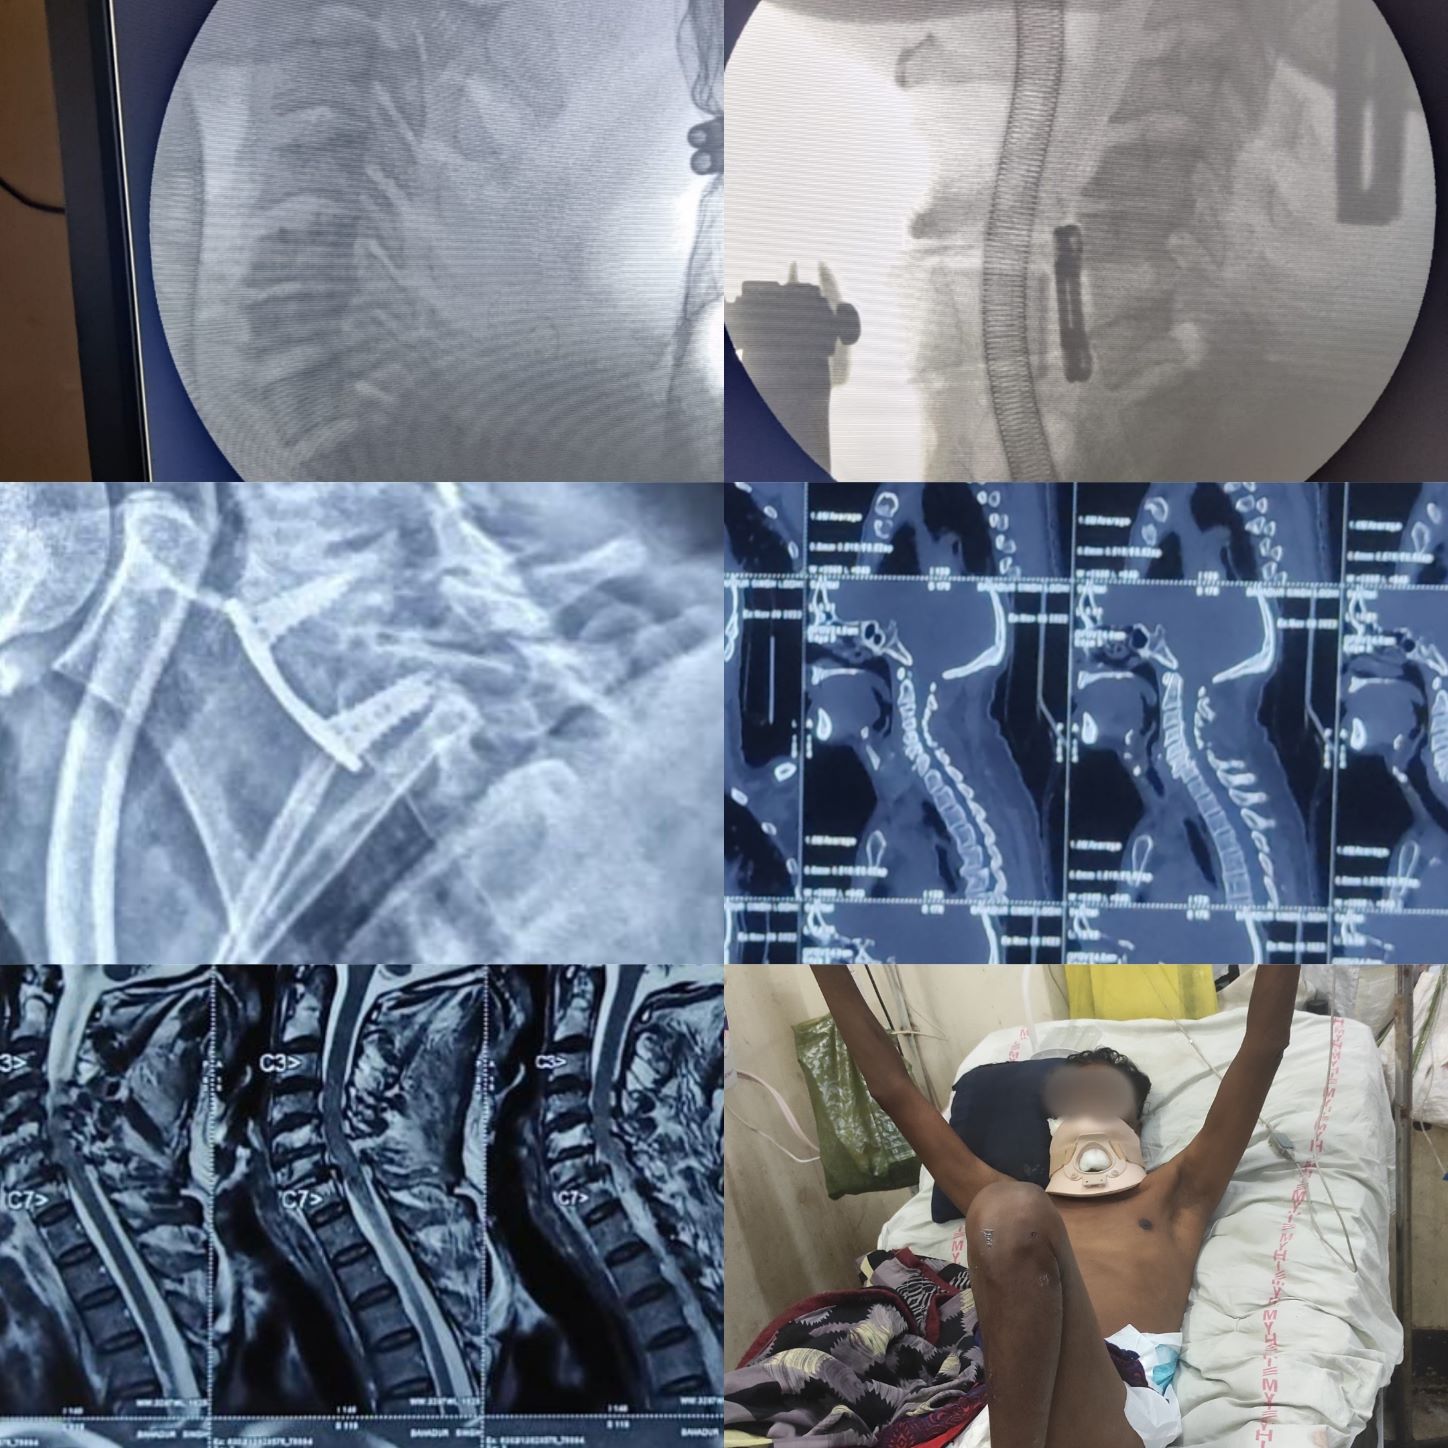

Gallery